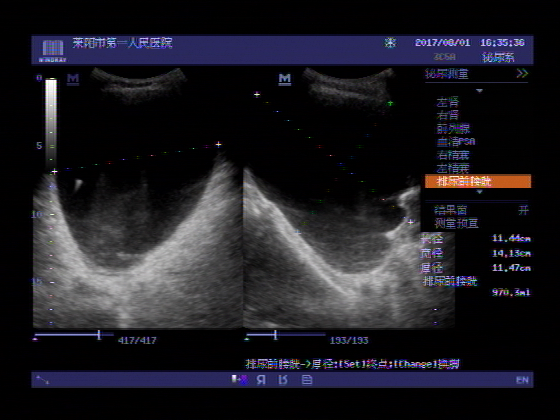

超声入门贴565前列腺增生并膀胱尿潴留

超声入门贴604前列腺增生并急性尿潴留